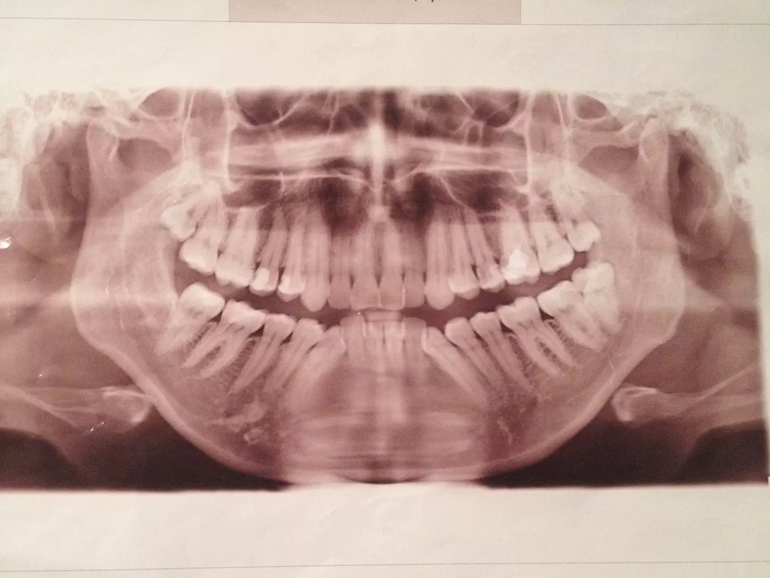

Вот с чего я начала лечение, в жизни не все так плохо смотрится как на фото))) (внизу конечно жуть) Фото сделано еще до удаления 8, сейчас уже нет 6 зубов))))